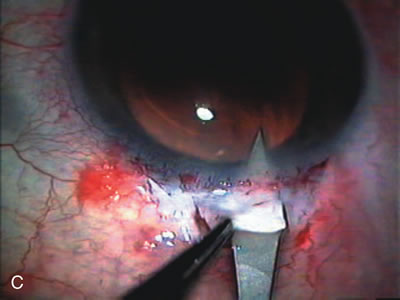

Fig. 4. Viscocanalostomy with deep sclerectomy and phacoemulsification. Nonpenetrating filtration procedures (NPFS) may be combined with phacoemulsification. Patients with mild disc damage and a history of limited topical drug therapy are the best candidates. Patients who require an IOP in the low teens are not good candidates for NPFS. By definition, NPFS is designed to lower IOP without penetrating into the anterior chamber, thereby avoiding the complications associated with trabeculectomy. Viscocanalostomy is intended to allow aqueous to percolate through a trabeculodescemetic membrane into a subscleral cavern created by the deep sclerectomy. The aqueous diffuses from the cavern into the dilated ostia of Schlemm's canal and into the episcleral venous plexus. A. Fashion a uniform 300-micron superficial scleral flap 1 mm into clear cornea. B. Construct a second 600-micron deep flap that facilitates the unroofing of Schlemm's canal, seen as the darker area. C. Use viscoelastic to dilate the ostia of Schlemm's canal. The major problem with viscocanalostomy is the eventual closure of the ostium decreasing flow to the episcleral plexus. D. Dissect the deep flap anteriorly into clear cornea creating the trabeculodescemetic membrane. This membrane is clearly seen between the scleral spur and the bend of the deep flap. The integrity of this membrane ensures the nonpenetrating portion of the surgery. Another problem with NPFS is the eventual fibrosis of this initially transparent membrane requiring goniopuncture. E. Deep sclerectomy gets its name from removal of the deep flap. Removal of this flap creates the potential subscleral space for accumulation of aqueous before it enters Schlemm's canal and exits the episcleral venous plexus. After removal of the deep flap, the superficial flap is sutured into place and conjunctiva closed. Approximately half of these procedures develop a shallow bleb.